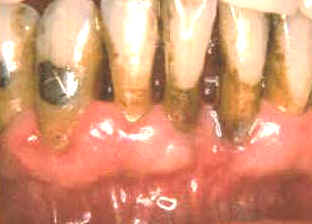

Este paciente es un varón 60 años de edad que

desea realizar tratamiento por implantes en el maxilar superior. Él

tiene un estándar socio-económico muy bueno, pero a pesar de esto,

demuestra un nivel de higiene dental muy deficiente. Las grandes

acumulaciones bacterianas están presentes a lo largo del margen

gingival en la mandíbula. Él ha perdido todos los dientes en el

maxilar superior y desea realizar implantes para así poder tener un prótesis

fija, que considera más confortable. |

El margen gingival de la mandíbula esta

intensamente inflamado y el tejido exhibe señales de daño

severo. En ciertas áreas del margen gingival se observan áreas de

necrosis . El margen gingival se encuentra retraído por la gran

cantidad de placa bacteriana y debido a esta acumulación de placa

dental hay bolsas poco profundas.

Las bacterias y las reacciones del huésped han causado un movimiento

apical del epitelio de unión con la cosnecuente pérdida de inserción

. En este caso particular el diagnóstico de las lesiones es fácil. |